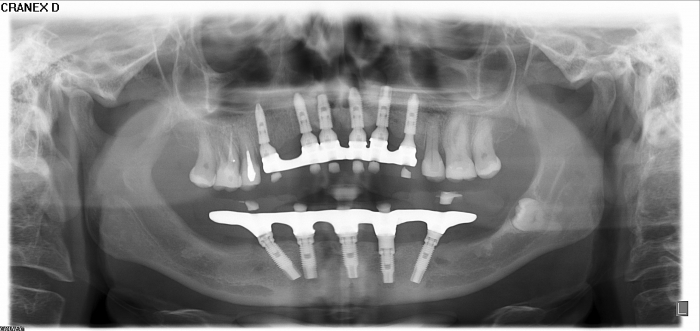

Raio -x inicial em 2014 - Clínica Cliniface

Raio -x inicial em 2014